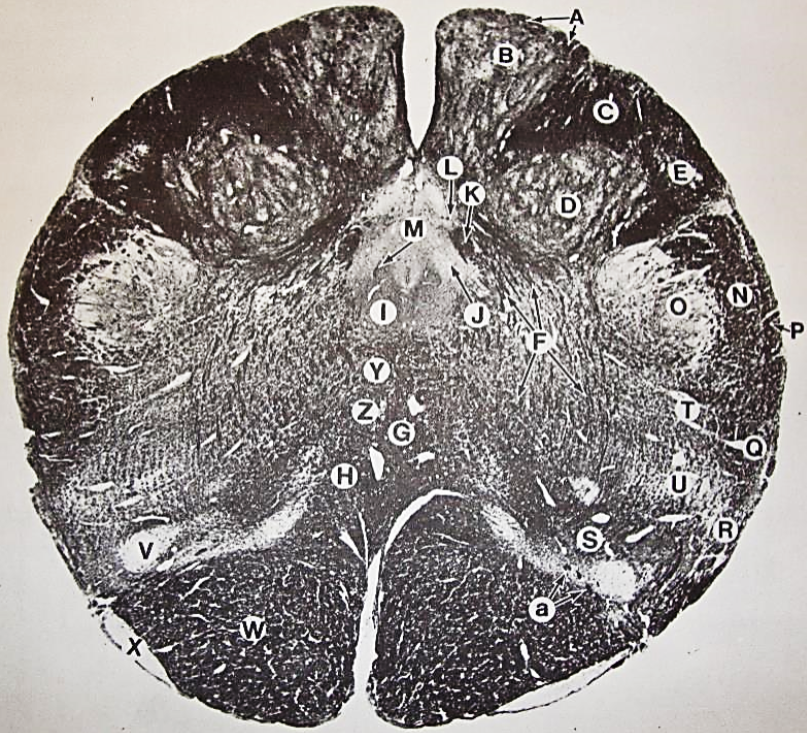

A

fasciculus gracilis

B

gracile nucleus

C

fasciculus cuneatus

D

cuneate nucleus

F

internal arcuate fibers

G

decussation of internal arcuate fibers

H

medial lemniscus

I

hypoglossal nucleus

J

dorsal motor nucleus vagus

K

solitary fasciculus

L

solitary nucleus

M

dorsal longitudinal fasciculus

N

spinal trigeminal tract

O

spinal trigeminal nucleus

P

posterior spinocerebellar tract

Q

anterior spinocerebellar tract

R

spinal lemniscus

S

lateral vestibulospinal tract

T

rubrospinal tract

U

lateral reticular nucleus

V

medial accessary olivary nucleus

W

pyramidal (corticospinal) tract

X

arcuate nucelus

Y

medial longitudinal fasciculus

Z

tectospinal tract

a

fascicles of hypoglossal nerve